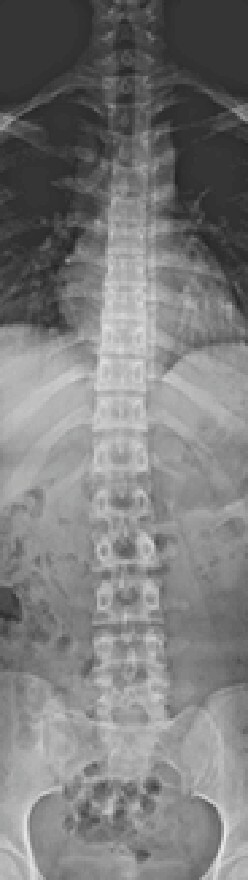

デジタルX線テレビシステム

従来より高画質で低線量なデジタルX線テレビシステムです。透視検査では人体の透過像を動画で観察し、X線写真を撮影します。消化器から整形外科まで幅広い領域の画像検査に対応しています。